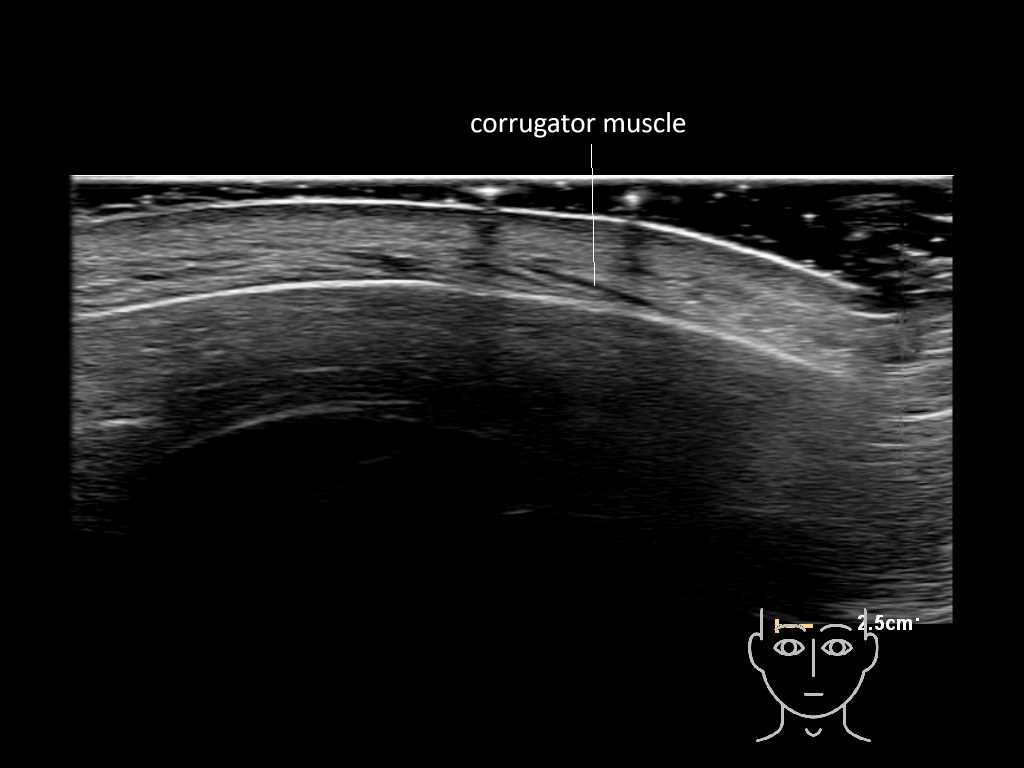

In this section you will learn more about the different layers of the face with the use of ultrasound. When you click on the secondary ultrasound image, you will see the different structures as an overlay. This will help to train yourself to recognize the different layers of the face.

Study the first image to recognize the different layers. If you are sure about the layers, swipe to the second image to view the answer (if applicable).